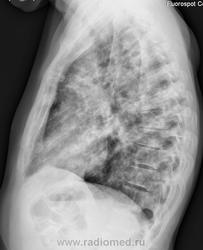

в тер. стационар. 41 год. Хр. алкоголизм, хр.панкреатит. Жалобы на кашель со скудной слизисто-гнойной мокротой, одышку, слабость. Считает себя больным со 2 мая 2011г. Т-38,0С, озноб, кашель. Лечился аугментином 7 дней. Состояние улучшилось. Кровь при поступлении: лейк.8,2*109 /л, Нв-112г/л. Ht-38,4. Т - 36,5С. Снимки №3 представлены. Ваше мнение коллеги о характере процесса в легких. С уважением Nikolas

В первую очередь необходимо думать о туберкулезном процессе, о банальной пневмонии - во вторую очередь.

Субъект с таким анамнезом и менталитетом может болеть чем угодно. На туберкулёз ОНО не очень похоже. Предположу аспирационную пневмонию.

На первое место (в наших условиях) поставил-бы, конечно, туберкулёз. Тщательное исследование мокроты на "палку"..., возможно и "гарнир" в виде "грибочков" будет найден. И не факт, что процесс старый...

Ну красавец! Думаю двусторонняя полисегментарная пневмония.

Пока за туберкулез.

Не устаю поражаться многоликим проялениям туберкулеза в рентгеновском отображении. Данный случай является подтверждением сказанному. В туберкулезной больнице установлен диагноз: диссеминированный туберкулез легких в фазе инфильтрации и распада, МБТ +. Благодарю коллег за высказанные мнения о возможной природе заболевания Я сомневался, так как, со словам матери больного, пациента год назад из другого терапевтического стационара уже переводили в ПТД. Выписали "с полным рассасыванием пневмонии". С уважением Nik